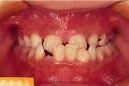

乱抗歯

Before

After